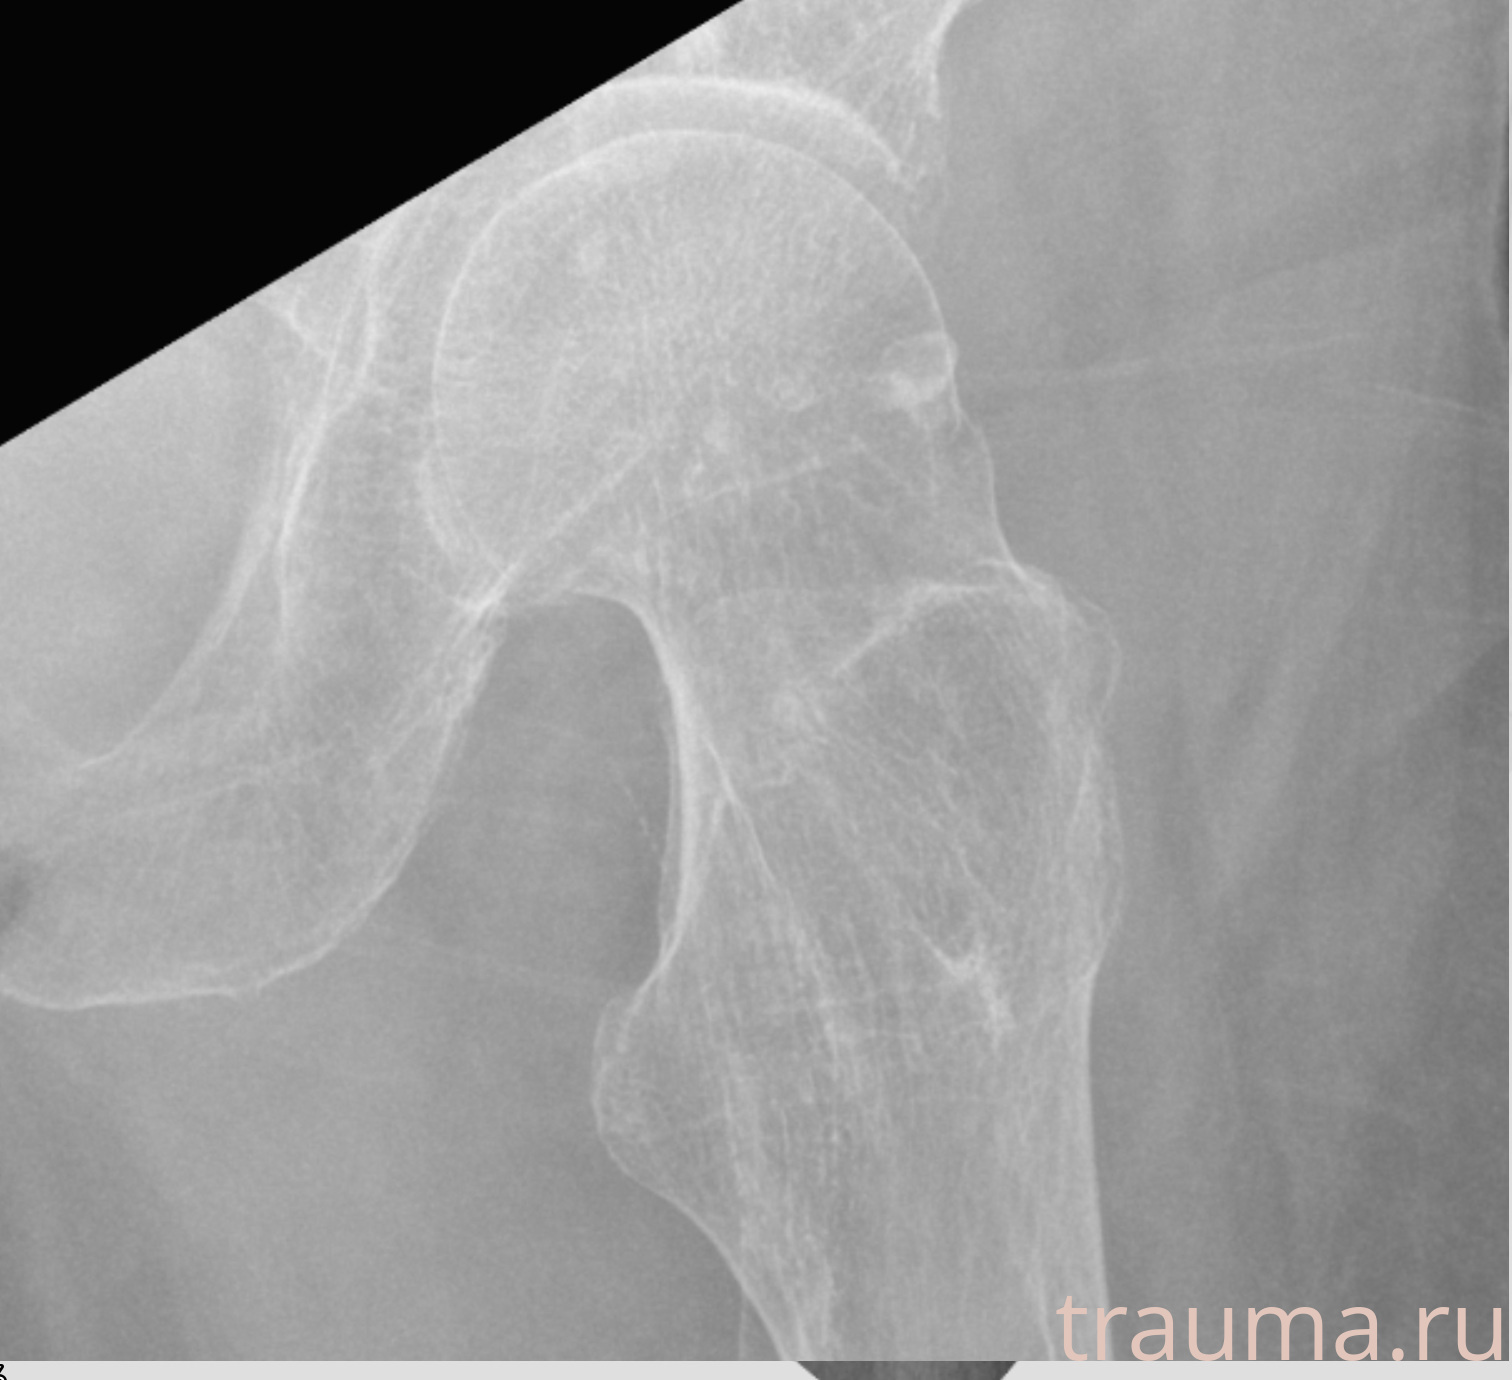

Первая помощь при переломе шейки бедра

Рентген на дому: по вашему адресу приезжает врач-рентгенолог, травматолог-ортопед с мобильным рентгеновским аппаратом, проводит диагностику травмы или заболевания, делает необходимые рентгенограммы, дает рекомендации по дальнейшему лечению. Получить качественные снимки в домашних условиях возможно благодаря уникальной методике, разработанной МосРентген Центром для института  Склифосовского